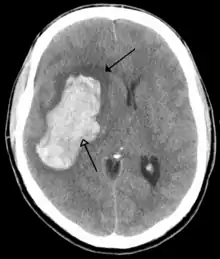

![]() | |

| CT scan of the brain showing a prior right-sided ischemic stroke from blockage of an artery. Changes on a CT may not be visible early on.[1] | |

The main risk factor for stroke is high blood pressure.[6] Other risk factors include tobacco smoking, obesity, high blood cholesterol, diabetes mellitus, a previous TIA, end-stage kidney disease, and atrial fibrillation.[2][6][7] An ischemic stroke is typically caused by blockage of a blood vessel, though there are also less common causes.[12][13][14] A hemorrhagic stroke is caused by either bleeding directly into the brain or into the space between the brain's membranes.[12][15] Bleeding may occur due to a ruptured brain aneurysm.[12] Diagnosis is typically based on a physical exam and supported by medical imaging such as a CT scan or MRI scan.[8] A CT scan can rule out bleeding, but may not necessarily rule out ischemia, which early on typically does not show up on a CT scan.[9] Other tests such as an electrocardiogram (ECG) and blood tests are done to determine risk factors and rule out other possible causes.[8] Low blood sugar may cause similar symptoms.[8]

CT scans may not detect an ischemic stroke, especially if it is small, of recent onset, or in the brainstem or cerebellum areas. A CT scan is more to rule out certain stroke mimics and detect bleeding.[9]